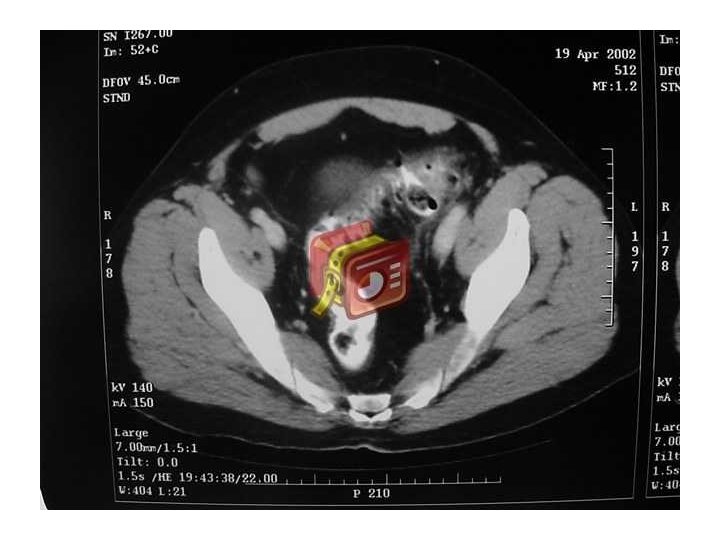

Diverticulitis • Inflamación divertículo y tejido pericolónico • 10 a 20% de los pacientes que conocen su enfermedad la desarrollan • Clínica: A veces pobre en el anciano – Dolor intenso abdominal (FII), irritación peritoneal, fiebre, abdomen quirúrgico. Leucocitosis – Perforación: absceso, neumaturia, fístulas • En diagnóstico útil Ecotomografía y TAC • Colonoscopía en frío confirmar patología y descartar neoplasia • 22– 30% de los individuos que presentan un primer episodio de diverticulitis presentarán un segundo episodio

Diverticulitis • Diagnóstico diferencial – Carcinoma de intestino – pielonefritis – EII – appendicitis – Colitis isquémica – Síndrome de colon irritable – Enfermedad inflamatoria pélvica

Divertículos de colon